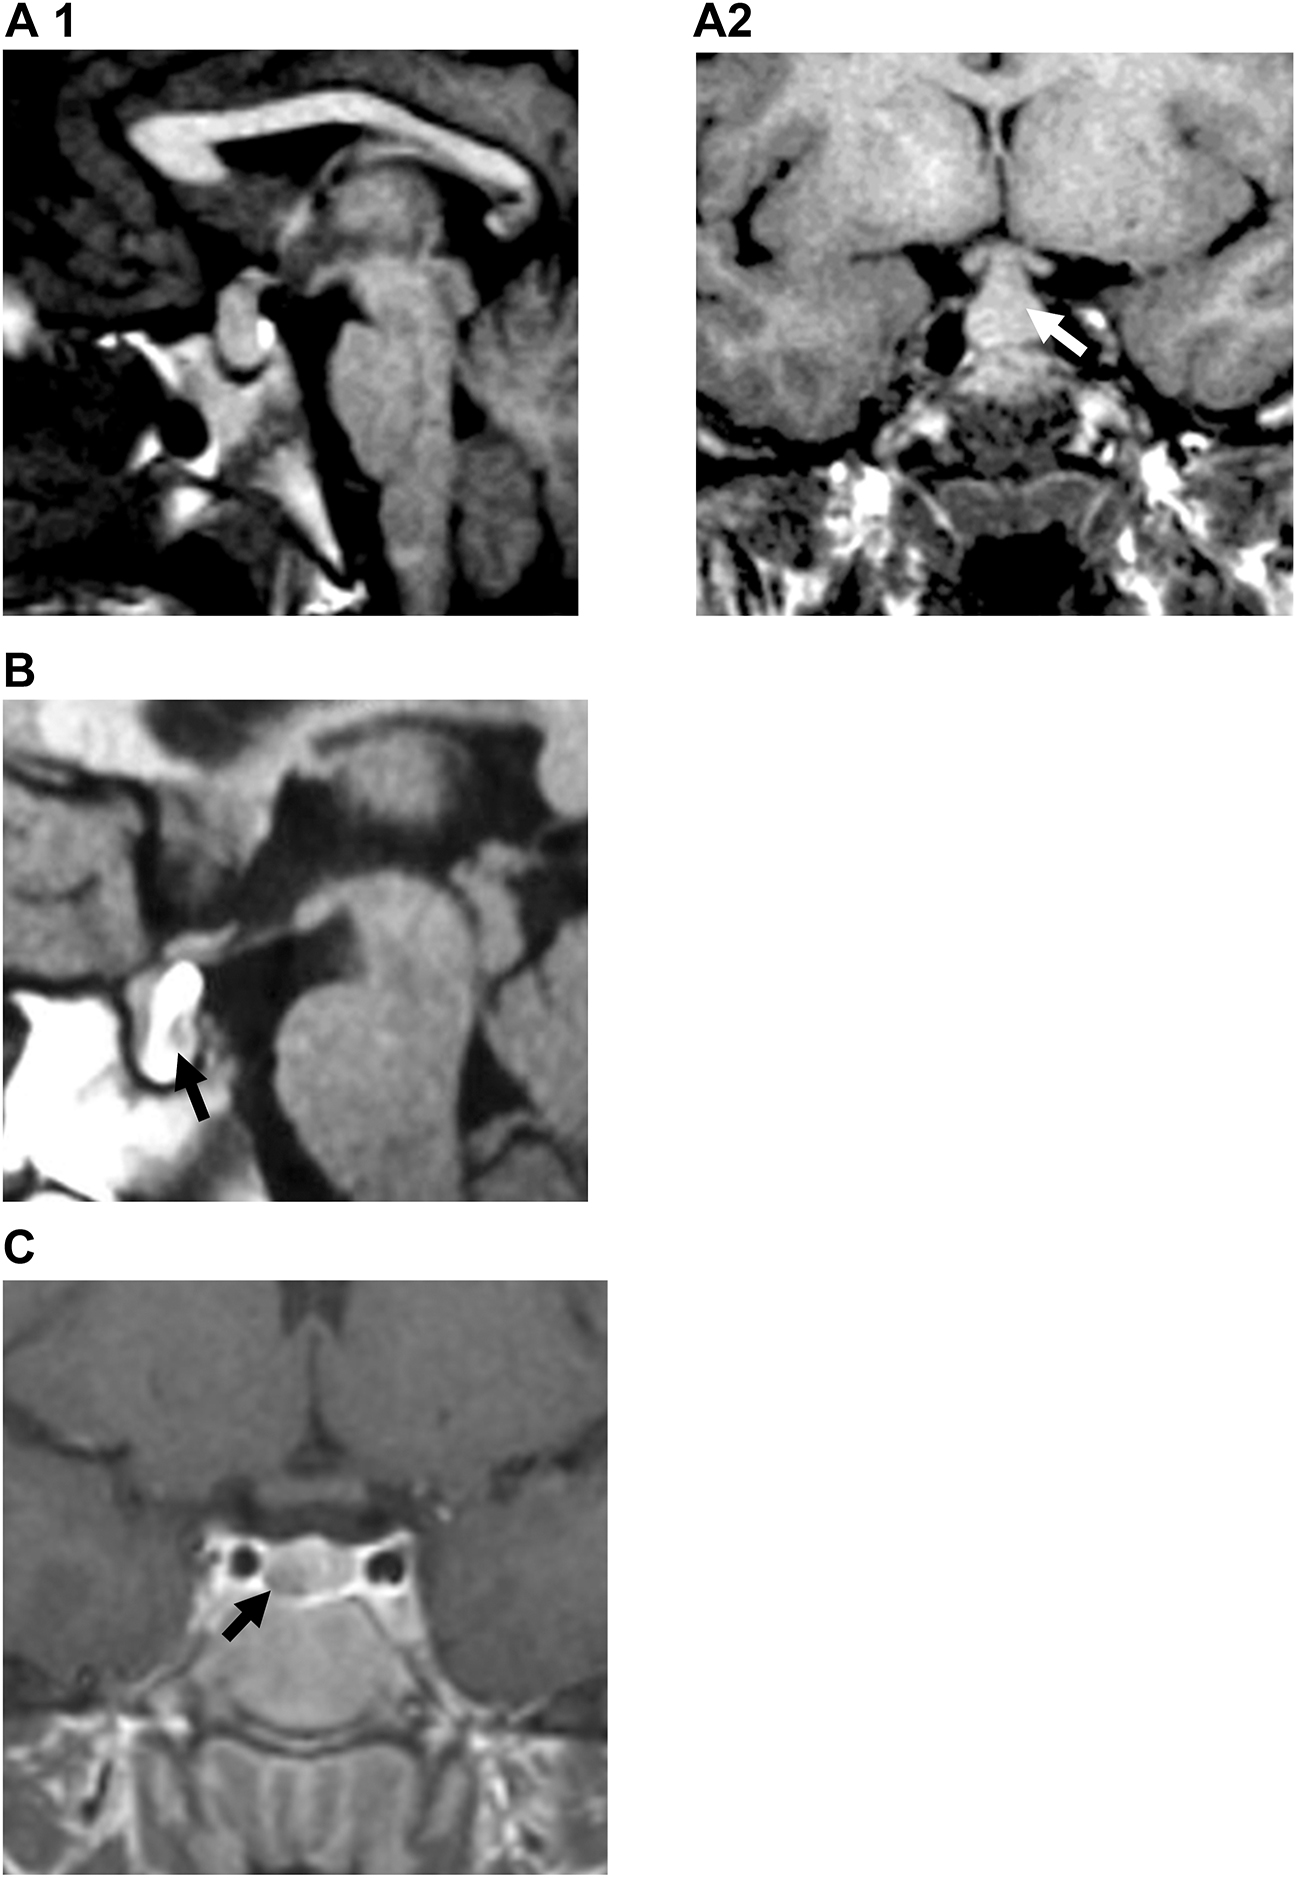

Reninoma: an unusual cause of growth failure

Nupoor Vaghasia, Ganesh Jevalikar, Mohammad Shafi Kuchay, Lipika Lipi, Ambrish Mithal

Page range: 73-78